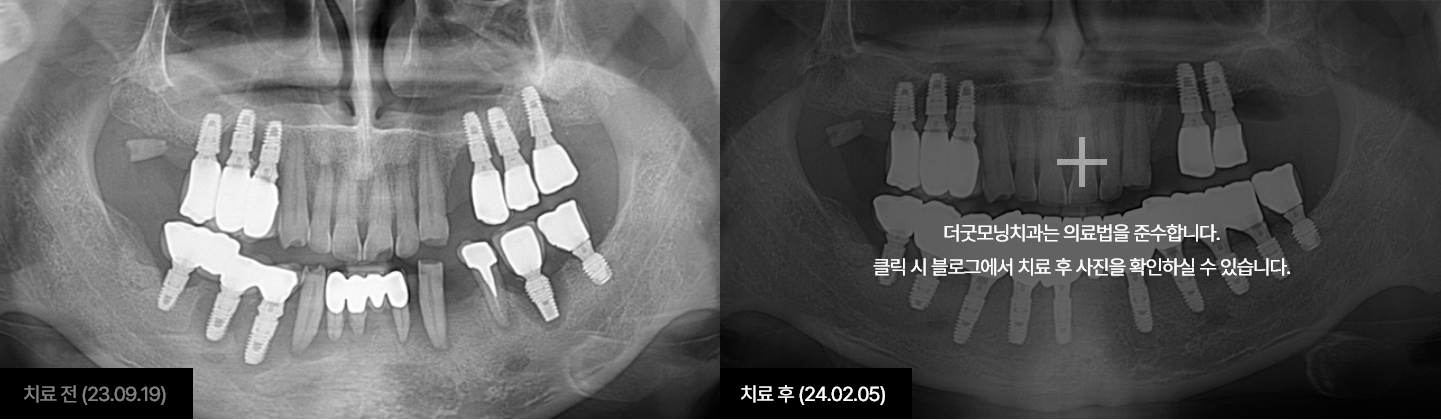

임플란트는 시술하는 의사의 수술 경험, 노하우에 따라 진료 결과가 달라지는

시술입니다.

잇몸뼈에 식립하여 자연치아를 대체해 주는 보철치료인 만큼

잇몸과

잇몸뼈에 대해 전문성이 높은 치주과 전문의가 진료해야 합니다.

더굿모닝치과는

보건복지부 인증 치주과+통합치의학과 더블보드 전문의가 직접 진료하며,

진단부터 식립, 최종 보철물까지 꼼꼼하게 완성해 드릴 것을

약속드립니다.